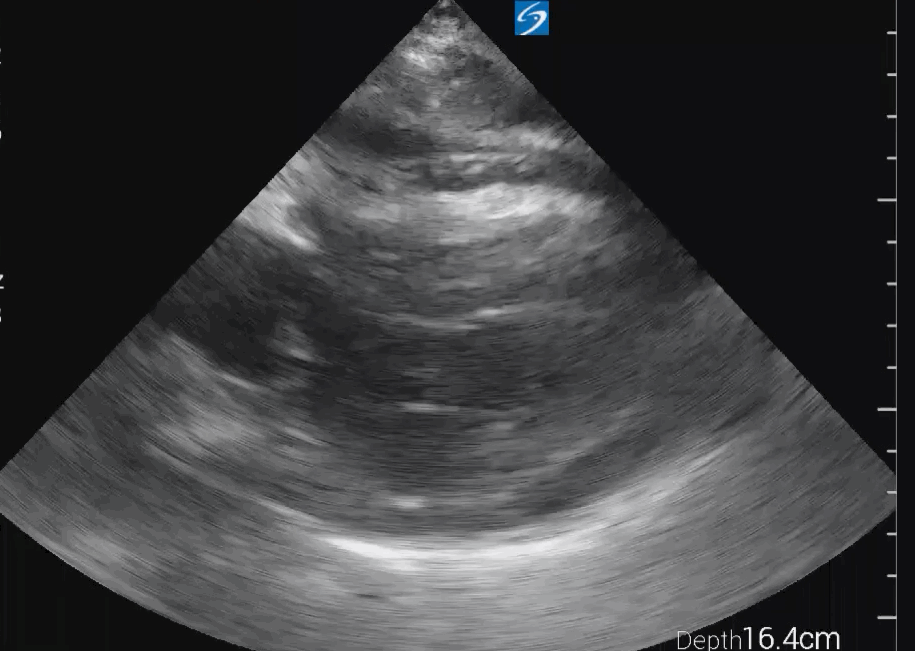

SC view

SC view of an empty left ventricle with severe hypertrophy: SC view from the same patient confirms the findings seen in the PLAX view. The left ventricle appears empty with severe hypertrophy, and muscular activity is present, indicating ongoing resuscitation efforts and the need to address the hypovolemic state. The small rim of pericardial effusion is also visible in this view, reinforcing the need for evaluation to determine if emergency drainage is warranted.